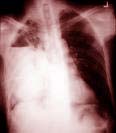

Chụp X quang bụng tổng quát không chuẩn bị cho thấy bóng gan to, cơ hoành bị đẩy lên cao (nếu là áp xe gan phải). Độ chênh lệch giữa cơ hoành (P) và (T) thường khoảng 2cm, hoặc ngoại lệ có thể vượt lên 8cm, góc sườn hoành (P) mờ do phản ứng màng phổi. X-quang phổi cho thấy có bất thường trong ½ các trường hợp áp-xe gan. Các dấu hiệu bất thường bao gồm: vòm hoành phải nâng cao, xẹp đáy phổi (P), tràn dịch màng phổi (P) với lượng dịch ít do phản ứng kích thích viêm. Tràn dịch màng phổi lượng nhiều cần chú ý là khối abces vở lên phổi.